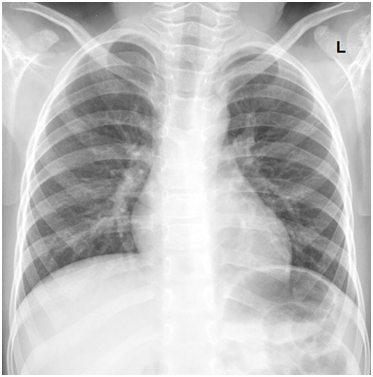

A 5-year-old male with a history of asthma presents with a three-days of cough, wheeze and worsening shortness of breath. The team must recognize severe asthma and initiate usual asthma treatment, but the child does not respond to these basic treatments and continues to worsen. The team should escalate management – epinephrine, magnesium, ketamine. The patient continues to tire and requires intubation. Post-intubation, the team must optimize ventilator settings/paralyze/bear hug. If not treated aggressively, the patient will become hypoxic and bradycardic, potentially leading to arrest.